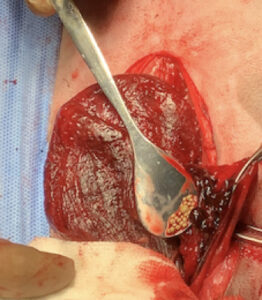

・膀胱頚部の不連続部より切開を加え、多数の小石状の結石を摘出

・結石鑑別:尿酸アンモニウム結石

・膀胱は全体的に赤褐色を呈し、生存性には疑問があった

・しかし、トリミング時に膀胱壁からのわずかではあるが出血を認め、血流はまだ保たれていると判断した

・膀胱壁の菲薄化は認められず、縫合に耐えうる組織強度が維持されていた

・損傷は膀胱頚部腹側に限局した局所的な病変であった

膀胱閉鎖術による温存が可能と判断した